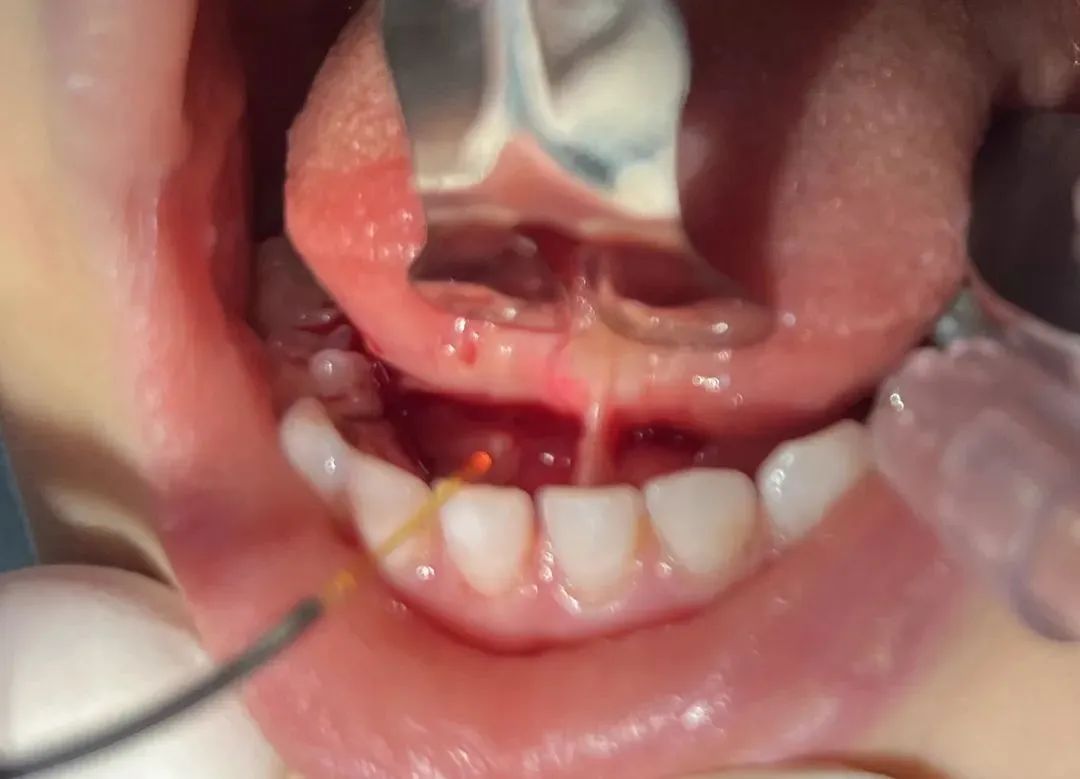

医院是中华医学会激光医学专委会副主委单位,在激光治疗口腔疾病方面有丰富的经验。相比传统手术方法,使用激光技术进行系带修整(如舌系带、唇系带过短的矫正)优势显著:

1)创伤小,出血少:激光的高能量可瞬间切割并封闭小血管,术中几乎不出血,无需缝合,减少了组织损伤和术后血肿的风险;

3)精度高,视野清晰:激光能量集中,可精准切割目标组织,不影响周围健康组织;且术中无出血干扰,医生视野更清晰,操作更精准;